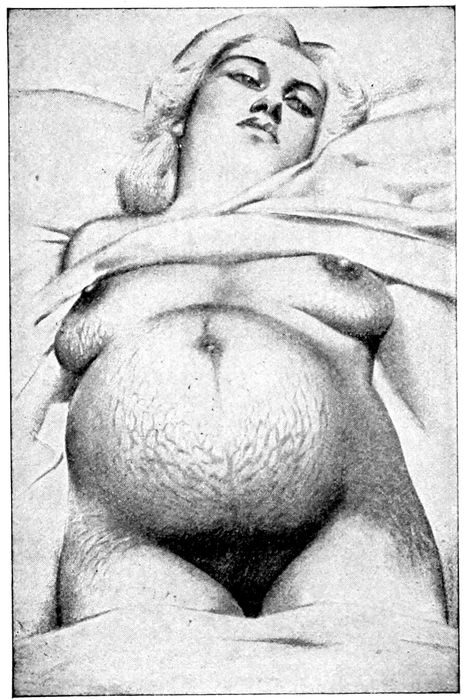

Fig. 25.—Striæ Gravidarum. (Edgar.)

Striæ Gravidarum.—Striæ gravidarum appear on the

abdomen similar to those observed on the breasts and

are due to the same cause—mechanical stretching.

When fresh, they are pinkish in color and variable in

length and breadth, but attain the greatest size below

55the umbilicus. Occasionally they extend to the thighs

and buttocks.

After labor, they become pale, silvery, and scar-like

and are called linea albicantes. They are sometimes

found in other conditions than pregnancy, such as tumors

or ascites.